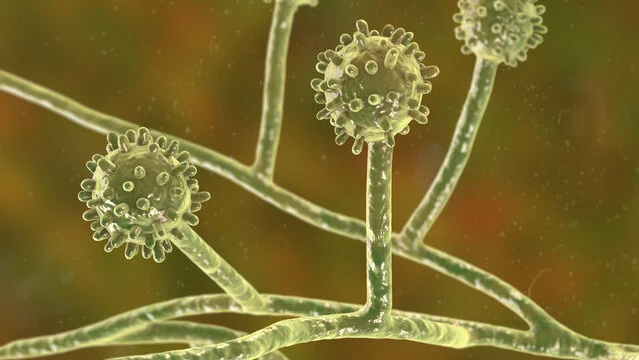

Ler mais Fungo

FungoEsporotricose

Micose subcutânea frequentemente associada ao contato com gatos infectados.

Ler mais Fungo

FungoCriptococose

Micose sistêmica relacionada a fungos presentes no ambiente e em excretas de aves.

Ler mais Fungo

FungoHistoplasmose

Micose sistêmica adquirida principalmente pela inalação de esporos.

Ler mais Fungo

FungoParacoccidioidomicose

Micose sistêmica endêmica da América Latina, com comprometimento pulmonar frequente.

Ler mais Bactéria